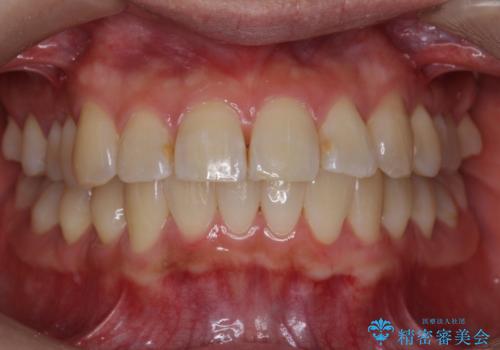

前歯と奥歯の反対咬合 部分ワイヤーとインビザラインで

上のワイヤー矯正を半年ほど行い反対咬合を改善してから、上下インビザライン治療を行いました。

下の前歯を中に入れるためにIPR(歯をわずかに削る処置)を行いました。

左上の反対咬合になっていた歯の頬側咬頭は、すでに削れて短くなっていましたがそのまま並べています。